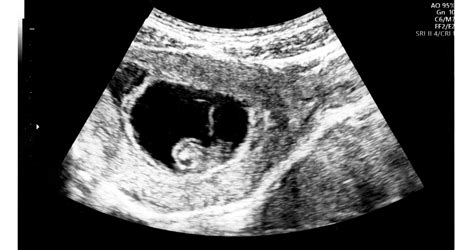

Ezek a jegyek már a magzati élet során is megjelenhetnek, és ultrahangvizsgálattal kimutathatók, ami felkeltheti a Down-szindróma gyanúját, de nem jelent biztos diagnózist.

- Kombinált szűrés: A terhesség első harmadában (trimeszterében) végzett vizsgálat, amely a magzati tarkóredő ultrahangos mérésén és az anyai vérben lévő két biokémiai jelző (szabad béta-hCG és PAPP-A) mérésén alapul. Ez az eljárás átlagosan 86-95%-os hatékonysággal szűri ki a rendellenességgel sújtott terhességeket.